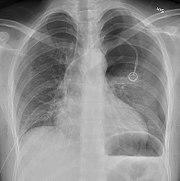

Chest X-ray showing a pneumothorax on the right (left in the image), where the absence of lung markings indicates that there is free air inside the chest

Chest X-ray showing the features of pneumothorax on the left side of the person (right in image)

A plain chest radiograph, ideally with the X-ray beams being projected from the back (posteroanterior, or "PA"), and during maximal inspiration (holding one's breath), is the most appropriate first investigation.[25] It is not believed that routinely taking images during expiration would confer any benefit.[26] Still, they may be useful in the detection of a pneumothorax when clinical suspicion is high but yet an inspiratory radiograph appears normal.[27] Also, if the PA X-ray does not show a pneumothorax but there is a strong suspicion of one, lateral X-rays (with beams projecting from the side) may be performed, but this is not routine practice.[14][18]

It is not unusual for the mediastinum (the structure between the lungs that contains the heart, great blood vessels, and large airways) to be shifted away from the affected lung due to the pressure differences. This is not equivalent to a tension pneumothorax, which is determined mainly by the constellation of symptoms, hypoxia, and shock.[13]

The size of the pneumothorax (i.e. the volume of air in the pleural space) can be determined with a reasonable degree of accuracy by measuring the distance between the chest wall and the lung. This is relevant to treatment, as smaller pneumothoraces may be managed differently. An air rim of 2 cm means that the pneumothorax occupies about 50% of the hemithorax.[14] British professional guidelines have traditionally stated that the measurement should be performed at the level of the hilum (where blood vessels and airways enter the lung) with 2 cm as the cutoff,[14] while American guidelines state that the measurement should be done at the apex (top) of the lung with 3 cm differentiating between a "small" and a "large" pneumothorax.[28] The latter method may overestimate the size of a pneumothorax if it is located mainly at the apex, which is a common occurrence.[14] The various methods correlate poorly but are the best easily available ways of estimating pneumothorax size.[14][18] CT scanning (see below) can provide a more accurate determination of the size of the pneumothorax, but its routine use in this setting is not recommended.[28]